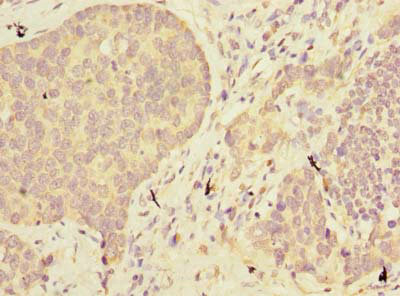

Immunohistochemistry of paraffin-embedded human gastric cancer using CSB-PA001094LA01HU at dilution of 1:100